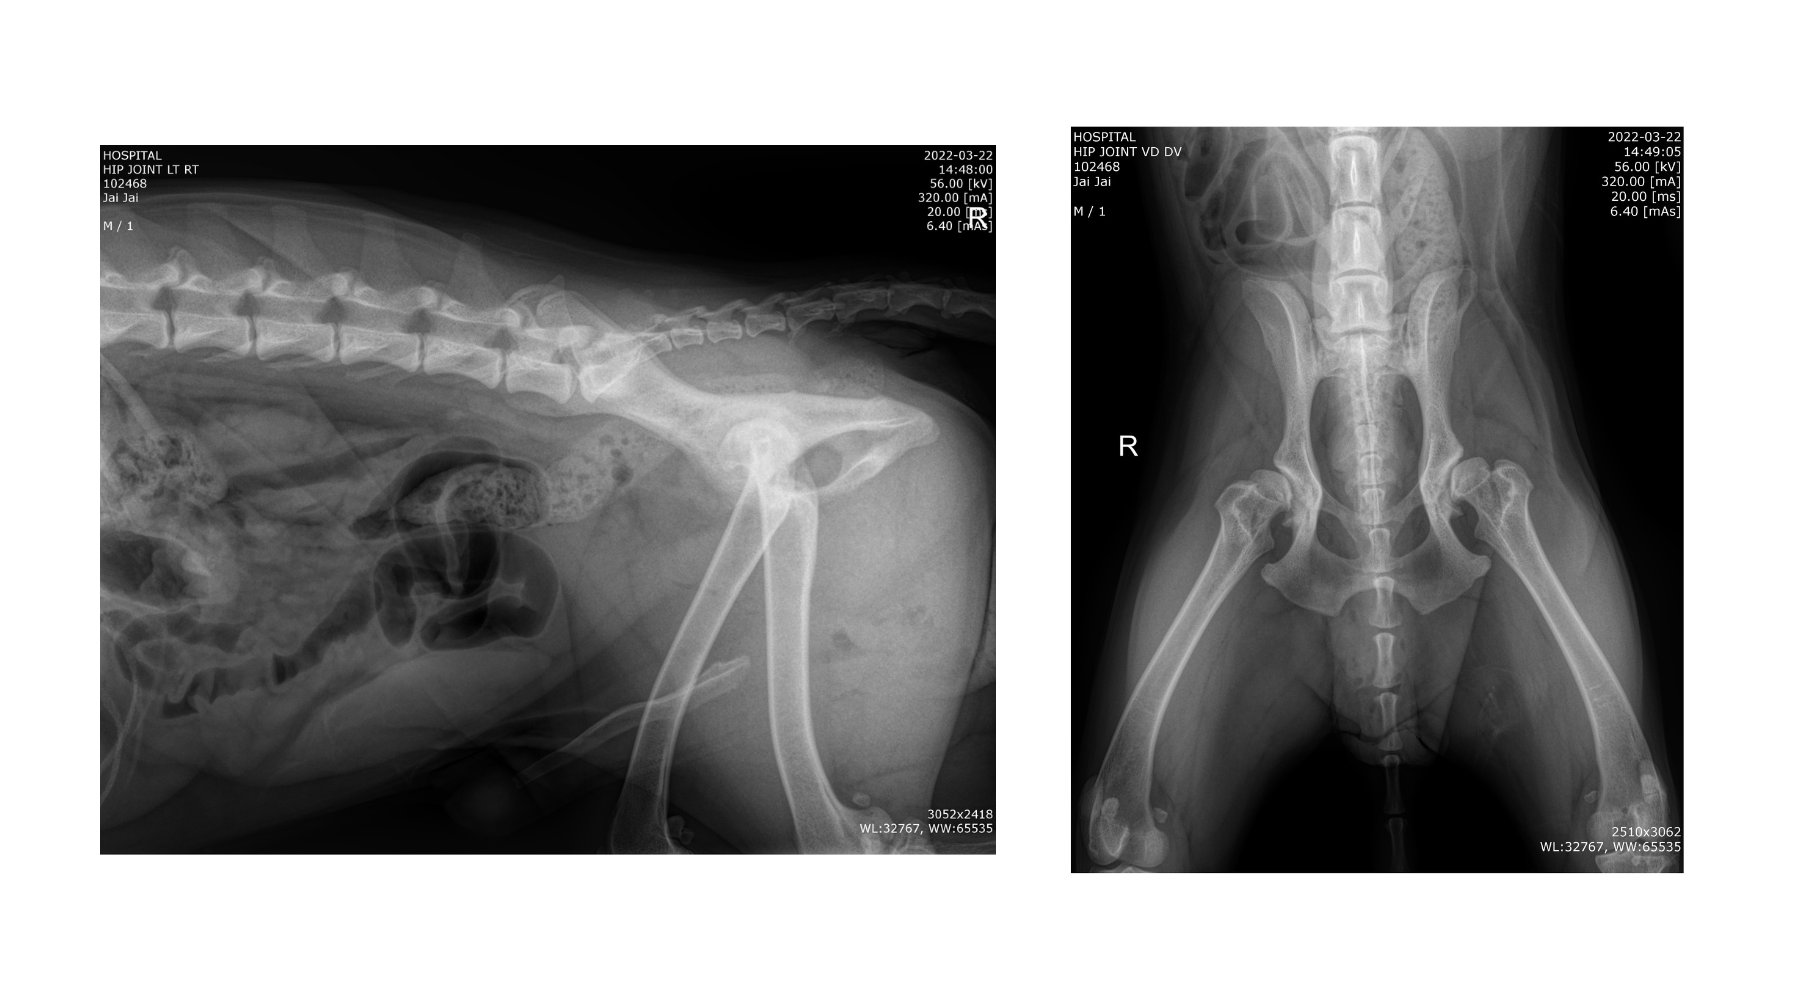

我們建議毛孩進行以下檢查,而主人可以自主選擇所需項目,以保安心。

對於雄性動物,術前檢查比較簡單,只需:

處理雌性動物需要加倍小心,並要事先確認:

做好術前檢查及準備後,獸醫就會安排毛孩進行絕育手術。獸醫會根據毛孩的體型與身體狀況,選擇最合適的切口方式與縫合技術,目的是確保手術安全、傷口穩定。